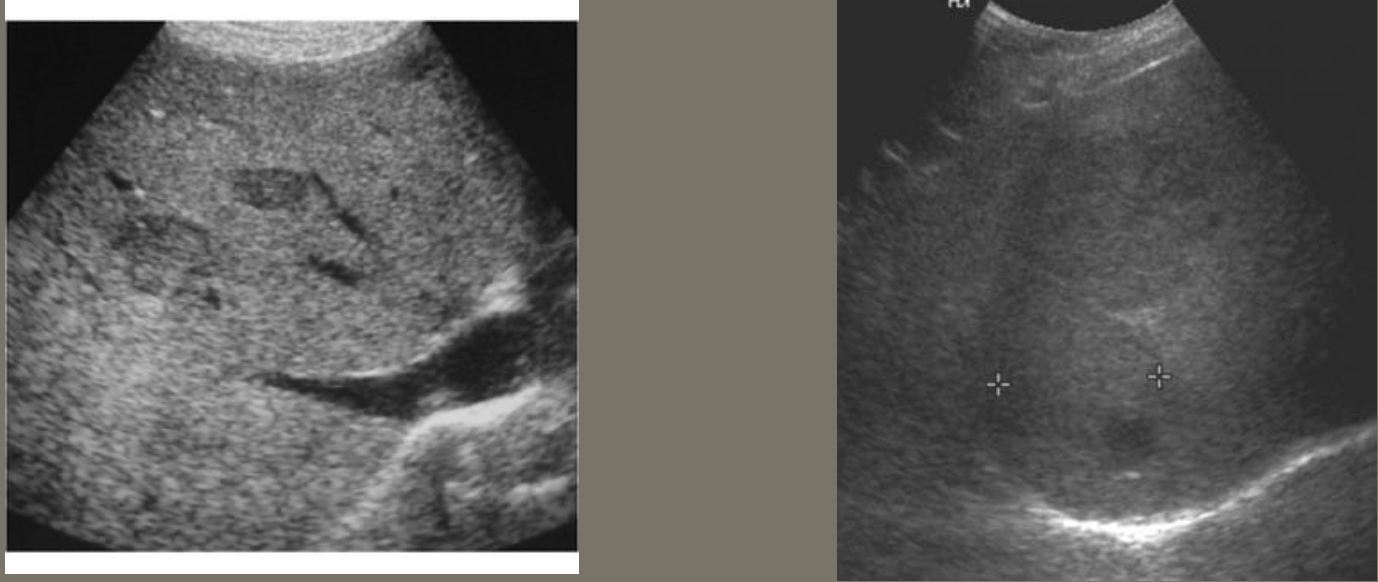

Aortic Dissection → intimal wall tears and allows blood flow between layers

2D US presentation: thin echogenic linear membrane fluttering in lumen creating a true and false lumen

color doppler: fill in both channels → pw shows regular flow in true and weak/no flow in false; asymmetrical kidney perfusion

DDX: AAA (focal dilation, no intimal flap)